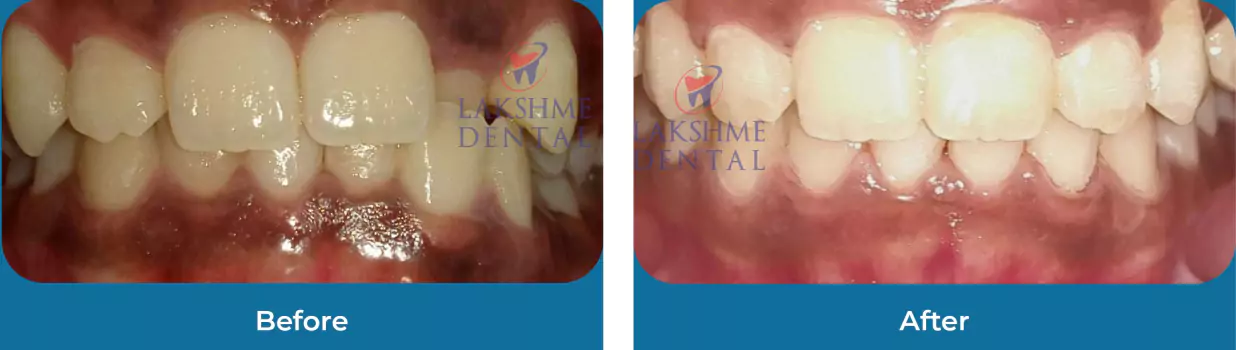

Esthetics

Full Mouth Rehabilitation